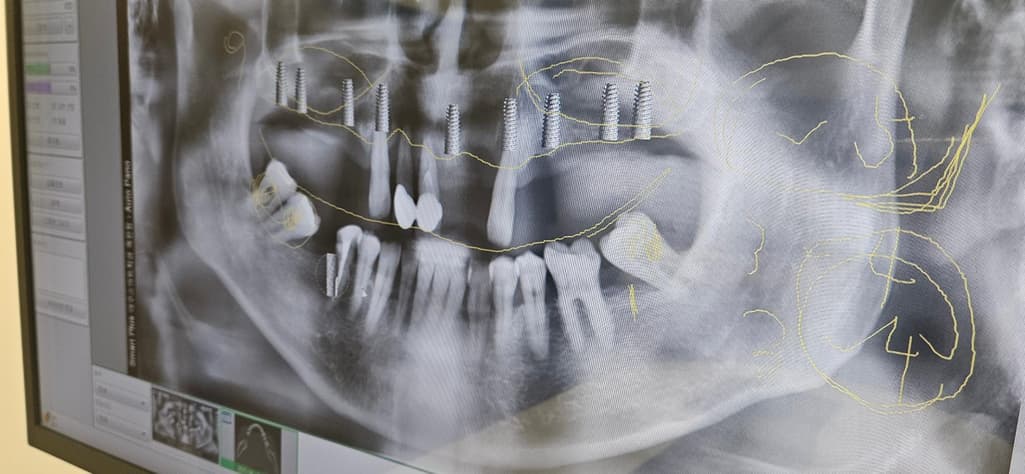

윗니 임플란트 9개 + 아랫니 1개, 사랑니 발치 2개, 상악동 거상술 포함

현재는 임플란트 고정체가 식립된 것으로 보입니다. 이런 경우에는 계약금을 환불해주기 어려울 수 있습니다. 또한 현재 시술된 임플란트 픽스처에 대한 비용을 추가적으로 수납을 해야 할 수도 있습니다.